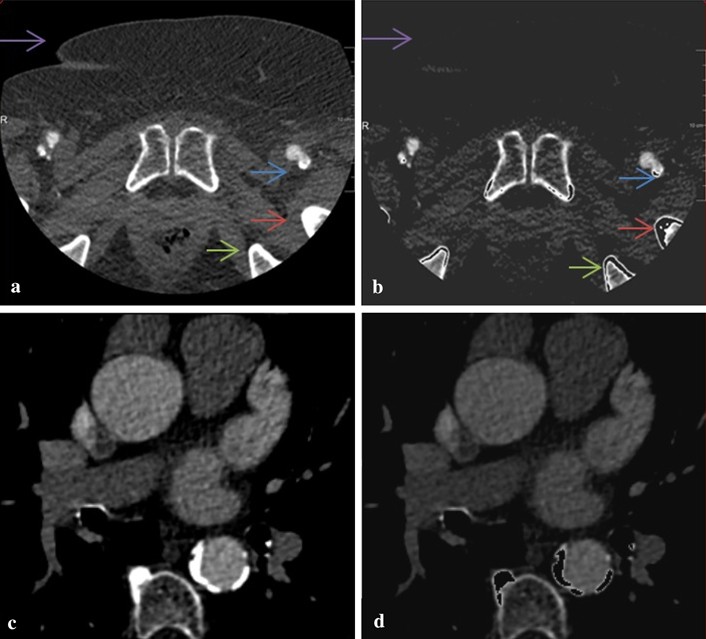

Based on this, an intensity profile of the voxels along our initially extracted centerline was extracted (Fig. 3). Next, a second order polynomial curve was fitted through the intensity profile data; this curve simulated the ideal case without calcium. Curve “b” in Fig. 3 shows this polynomial fit curve. Also shown is curve “a” which is an upward shifted version of curve “b” obtained by adding a constant value proportional to the standard deviation (SD) of the intensities in the profile. The values on curve “a” were used as the intensity threshold values for the high intensity structures (e.g. calcium) on the corresponding image slices along the vessel centerline. A similar method was used to find the tissue with lower intensity than the contrast-filled lumen using curve “c” which is a downward shifted version of curve “b”. Figure 4 shows examples of the original and mask slices in the CTA data using this method.

Examples of pre-processed slices. a Original femoral artery image. b Processed femoral artery image. c Original aorta image. d Processed aorta image. The purple arrows in (a) and (b) indicate low intensity tissue that has been removed in processed image, other arrows indicate the processed high intensity tissue